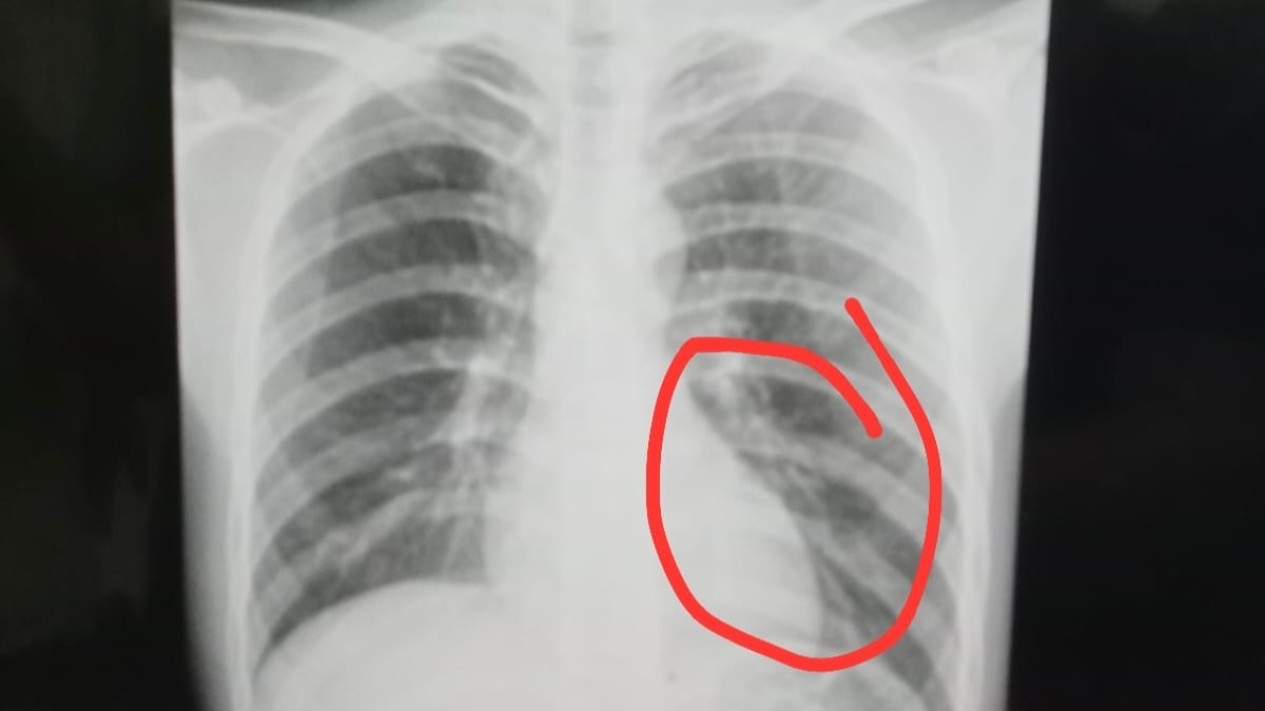

pemain Perseta Tulungagung bernama Firman Nugraha mengalami cedera serius berupa retak tulang dada